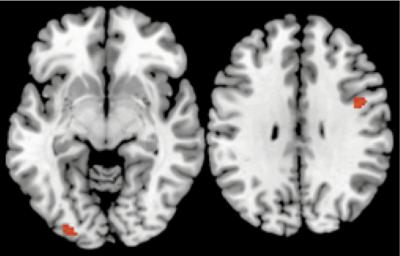

New brain imaging research from Carnegie Mellon University provides some of the first evidence showing how the brain unconsciously processes decision information in ways that lead to improved decision making. Credit: Carnegie Mellon University

When faced with a difficult decision, it is often suggested to “sleep on it” or take a break from thinking about the decision in order to gain clarity. But new brain imaging research from Carnegie Mellon University, published in the journal “Social Cognitive and Affective Neuroscience,” finds that the brain regions responsible for making decisions continue to be active even when the conscious brain is distracted with a different task. The research provides some of the first evidence showing how the brain unconsciously processes decision information in ways that lead to improved decision-making.